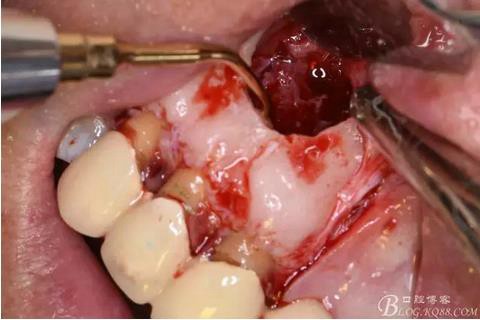

圖9.去除唇側(cè)薄的骨壁,暴露出囊壁

圖10.剝離囊壁